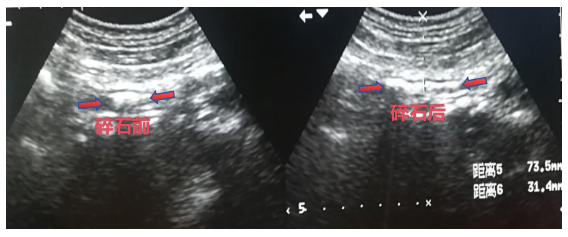

啪……就碎了……

啪……体外碎石治疗室里传来一阵规律的节奏声,患者还清醒八醒的,是在干什么?“哦哟,听到那个声音就觉得痛!”原来是在做体外冲击波碎石治疗(ESWL),它能利用高能...